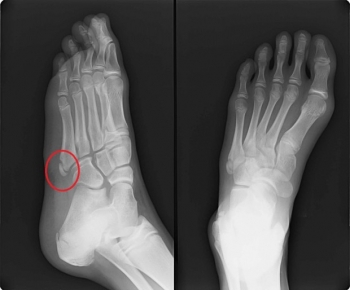

ヒトの中足骨は、左右の足根骨の遠位に5本ずつ存在する細長い管状骨で、趾節骨より長く、内側から外側へ向けて第1 - 第5趾と対応して、第1中足骨、第2中足骨、第3中足骨、第4中足骨、第5中足骨と呼ばれます。

第1中足骨が最も短く、最も太い。第2中足骨が最も長い。第3、第4、第5中足骨の順で短くなる。中足骨は中足骨頭(遠位端)・中足骨底(近位端)・中足骨体(骨幹部)の3つの部分に分けられます。

中足骨骨折

中足骨骨骨折の発生機序

直達外力では、重量物の落下、轢過などによる

介達外力では踏み外し時の内がえし外力による短腓骨筋の急激な収縮による第5中足骨基底部剥離骨折(下駄骨折と呼ばれる)が代表的です

第5中足骨近位骨幹部での骨折はジョーンズと呼ばれ、遷延治癒や偽関節になりやすい。